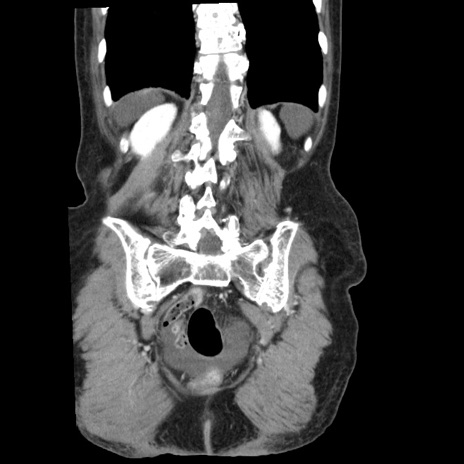

症例1(冠状断像)

【症例】80歳代女性

【主訴】腹痛

【現病歴】8時間前から腹痛あり来院。

【既往歴】糖尿病、脂質異常症、子宮体癌にて子宮全摘術

【身体所見】意識清明・会話良好だが腹痛で苦悶様、全腹部にわたって反跳痛と圧痛あり

【データ】WBC 13600、CRP 0.14、LDH 224、CK 90